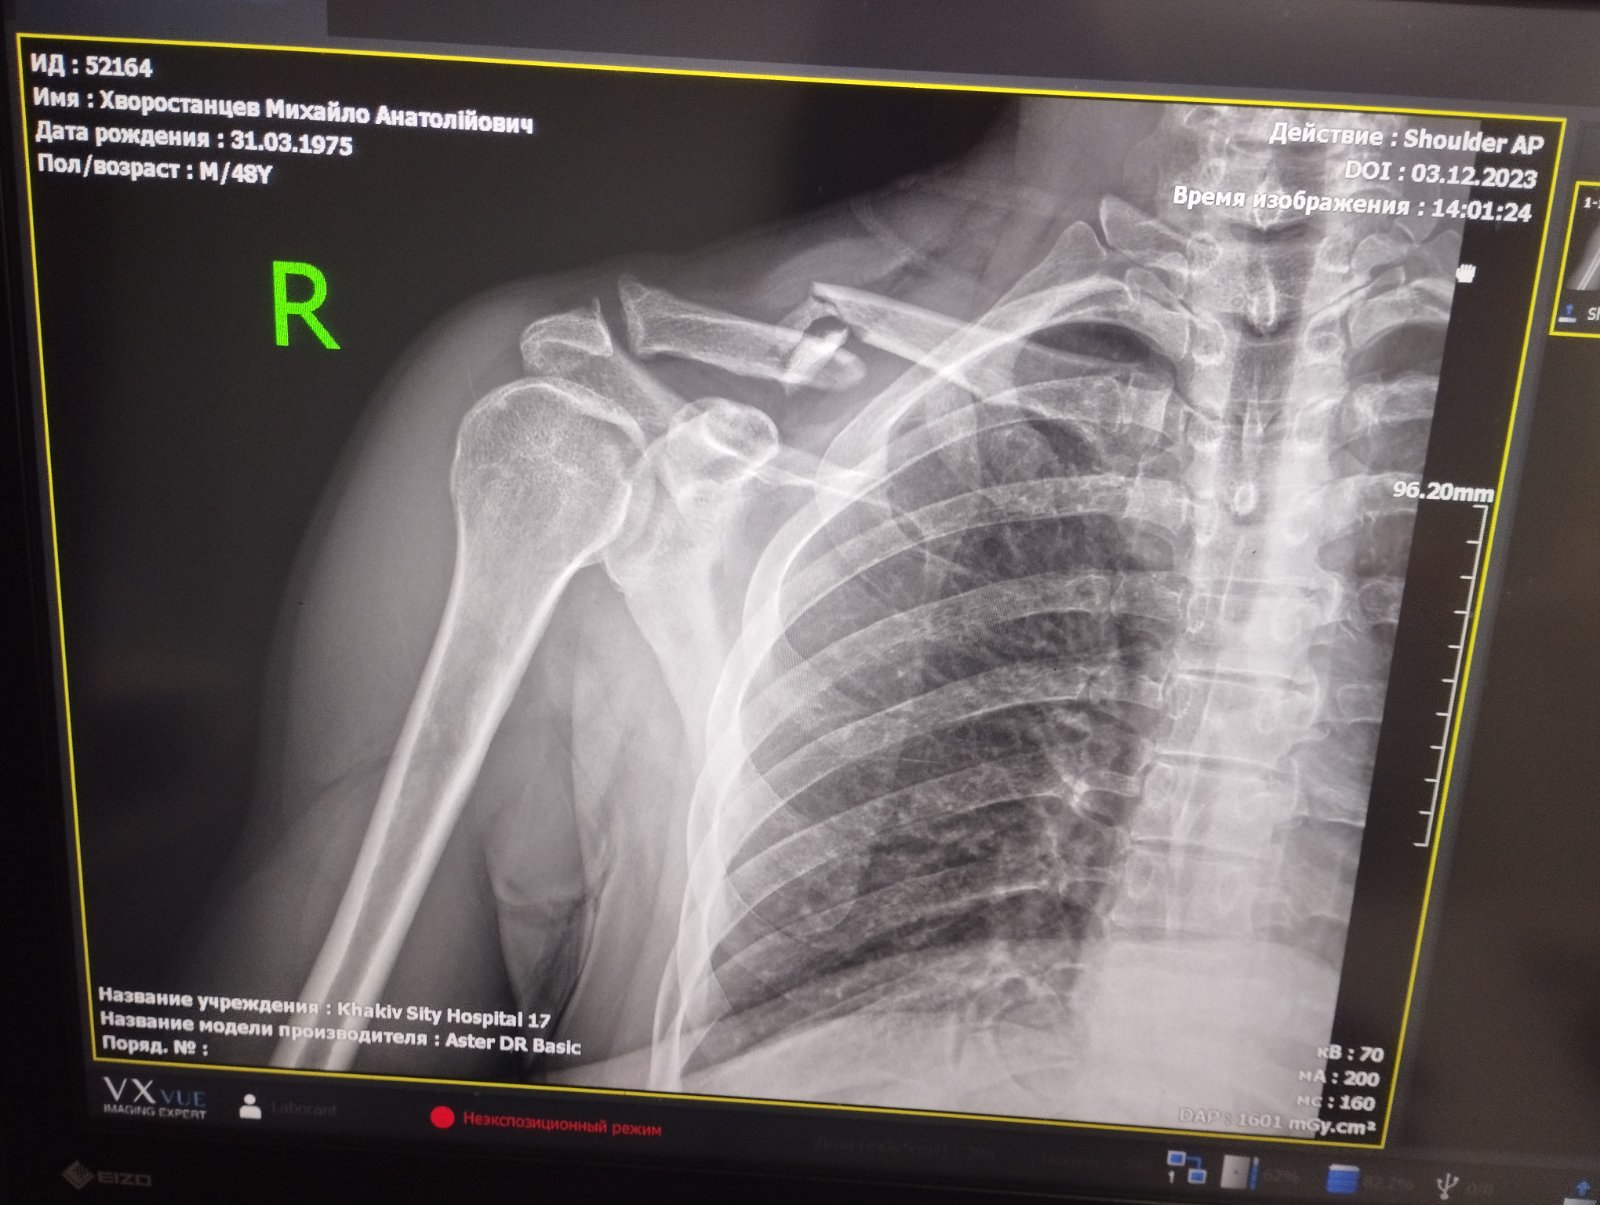

Гравець нашого турніру, арбітр та представник команди ПК ВЧД-5 Михайло Хворостанцев під час матчу отримав важку травму - перелом ключиці зі зімщенням. За висновком лікарів, Михайла очікує дорога операція та довгий процес реабілітації. Просимо всіх небайдужих підтримати фінансово